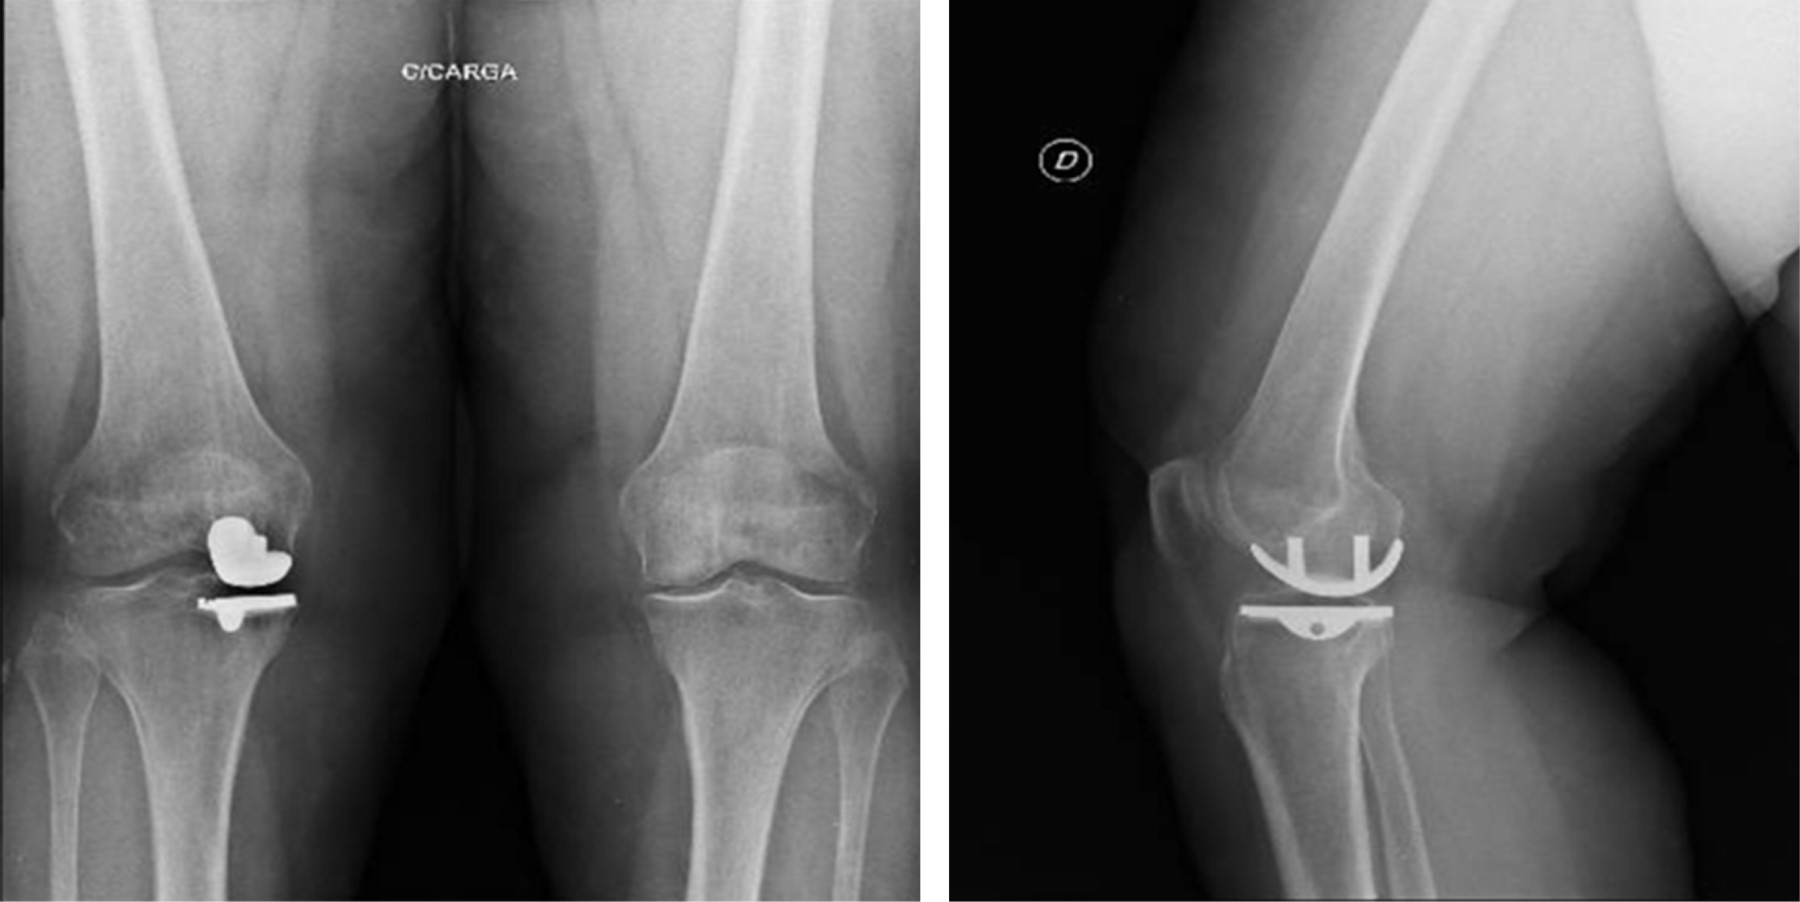

Figure 7

Figure 8

Figure 9